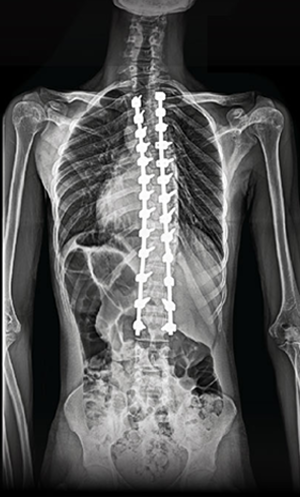

The procedure involves repositioning the spine and securing it with Screws and Rods. Bone graft is then placed so the treated vertebrae gradually heal together into one solid segment. This creates long-term stability, preventing further curve progression and improving overall alignment.

Gallery : Before - After

After

Before